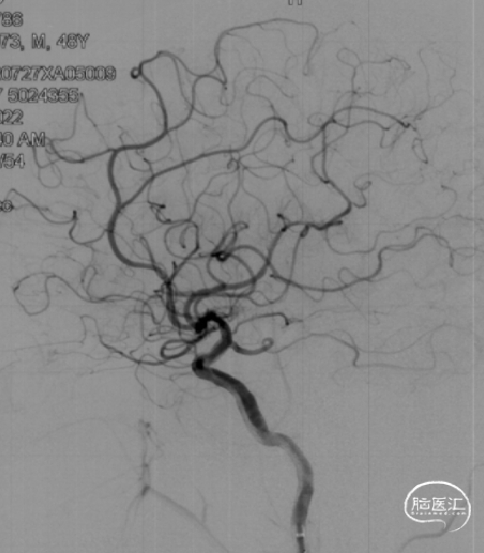

➤术前DSA检查

右侧大脑中动脉重度狭窄,左侧前循环未见明显异常。

病变部位: 右侧大脑中动脉M1段重度狭窄;狭窄率: 75.6%;狭窄长度: 6.10mm;参考远端血管直径: 1.27mm。

2022-07-27 术前正位

2022-07-27 术前侧位